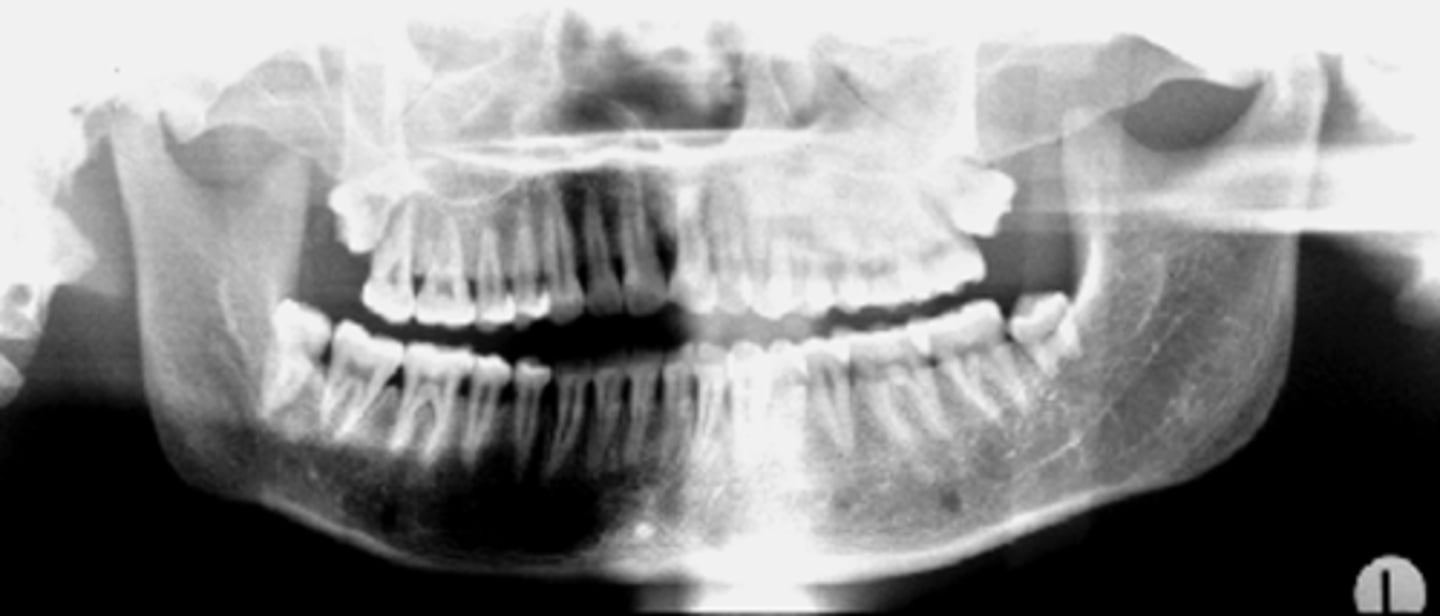

ID the positional error from the radiograph:

too far back (short/wider incisors)

(and right rotation)